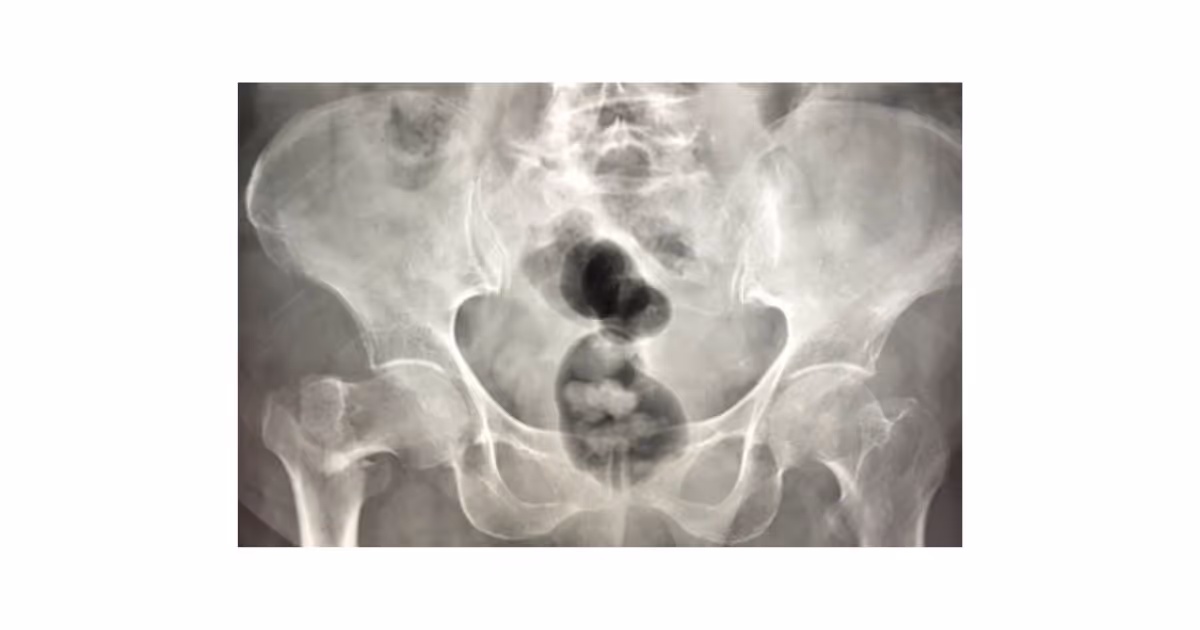

Seek medical attention if you experience symptoms indicating hip fractures such as hip pain, not being able to move or put weight on the injured leg or the injured leg appearing to be foreshortened. In patients with nondisplaced fractures, the pain or discomfort may be mild and full weight bearing may be possible. But if left untreated, the injury can further aggravate. It is recommended to see your doctor for further investigations. Your doctor will ask you about your medical conditions, perform a physical exam and obtain an X-ray to confirm the diagnosis.